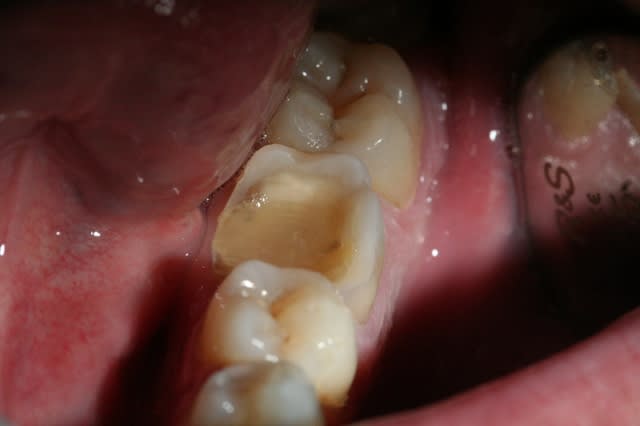

dépose du systemp onlay (trés pratique, se détache bien)

situation clinique

est ce que l'onlay est vraiment une solution sur des dents dévitalisées aussi délabrées que celle ci?

Img 1744 z0evts - Eugenol

je ne suis pas sure non plus que dans ce cas l'indication soit bonne.

on le voit peut être mal sur les photos mais il reste encore pas mal de tissu dentaire à conserver avant de se jeter comme un loup sur une brebis pour faire une couronne.

Il faut temporiser, proposer d'autres alternatives aux gens. Ici, ce patient n'avait pas de complémentaire, alors entre une ccm à 500 remboursée 96.75 et un onlay à 300 remboursé 35 environ , le patient a choisit.

En l'occurrence, dent dépulpée/2 parois résiduelles il s'agit d'une indication de coiffe périphérique (couronne) et vu les limites à peine juxta, je dirais même ancrage radiculaire...